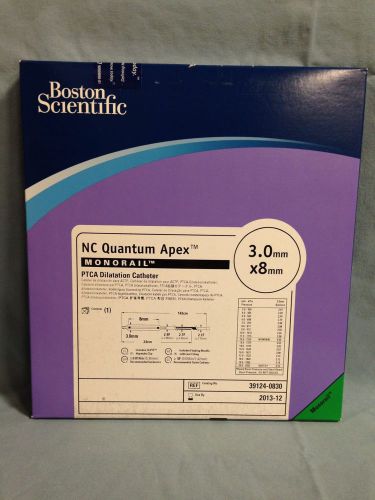

Boston Scientific NC Quantem Apex #39124-0830